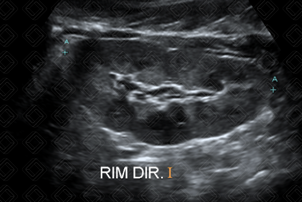

Texto alternativo para a imagem Figura 3. Créditos: Dra. Elazir Mota - Rio de Janeiro/RJ

Texto alternativo para a imagem Figura 4. Créditos: Dra. Elazir Mota - Rio de Janeiro/RJ

Descrição das figuras 3 e 4: Ultrassonografia do aparelho urinário pós-natal confirmando a presença de múltiplos cistos, não comunicantes e tamanhos variados na loja renal esquerda, associado à ausência de parênquima renal deste lado. A avaliação do rim contralateral é de suma importância e, nesse caso, o rim direito encontrava-se normal.